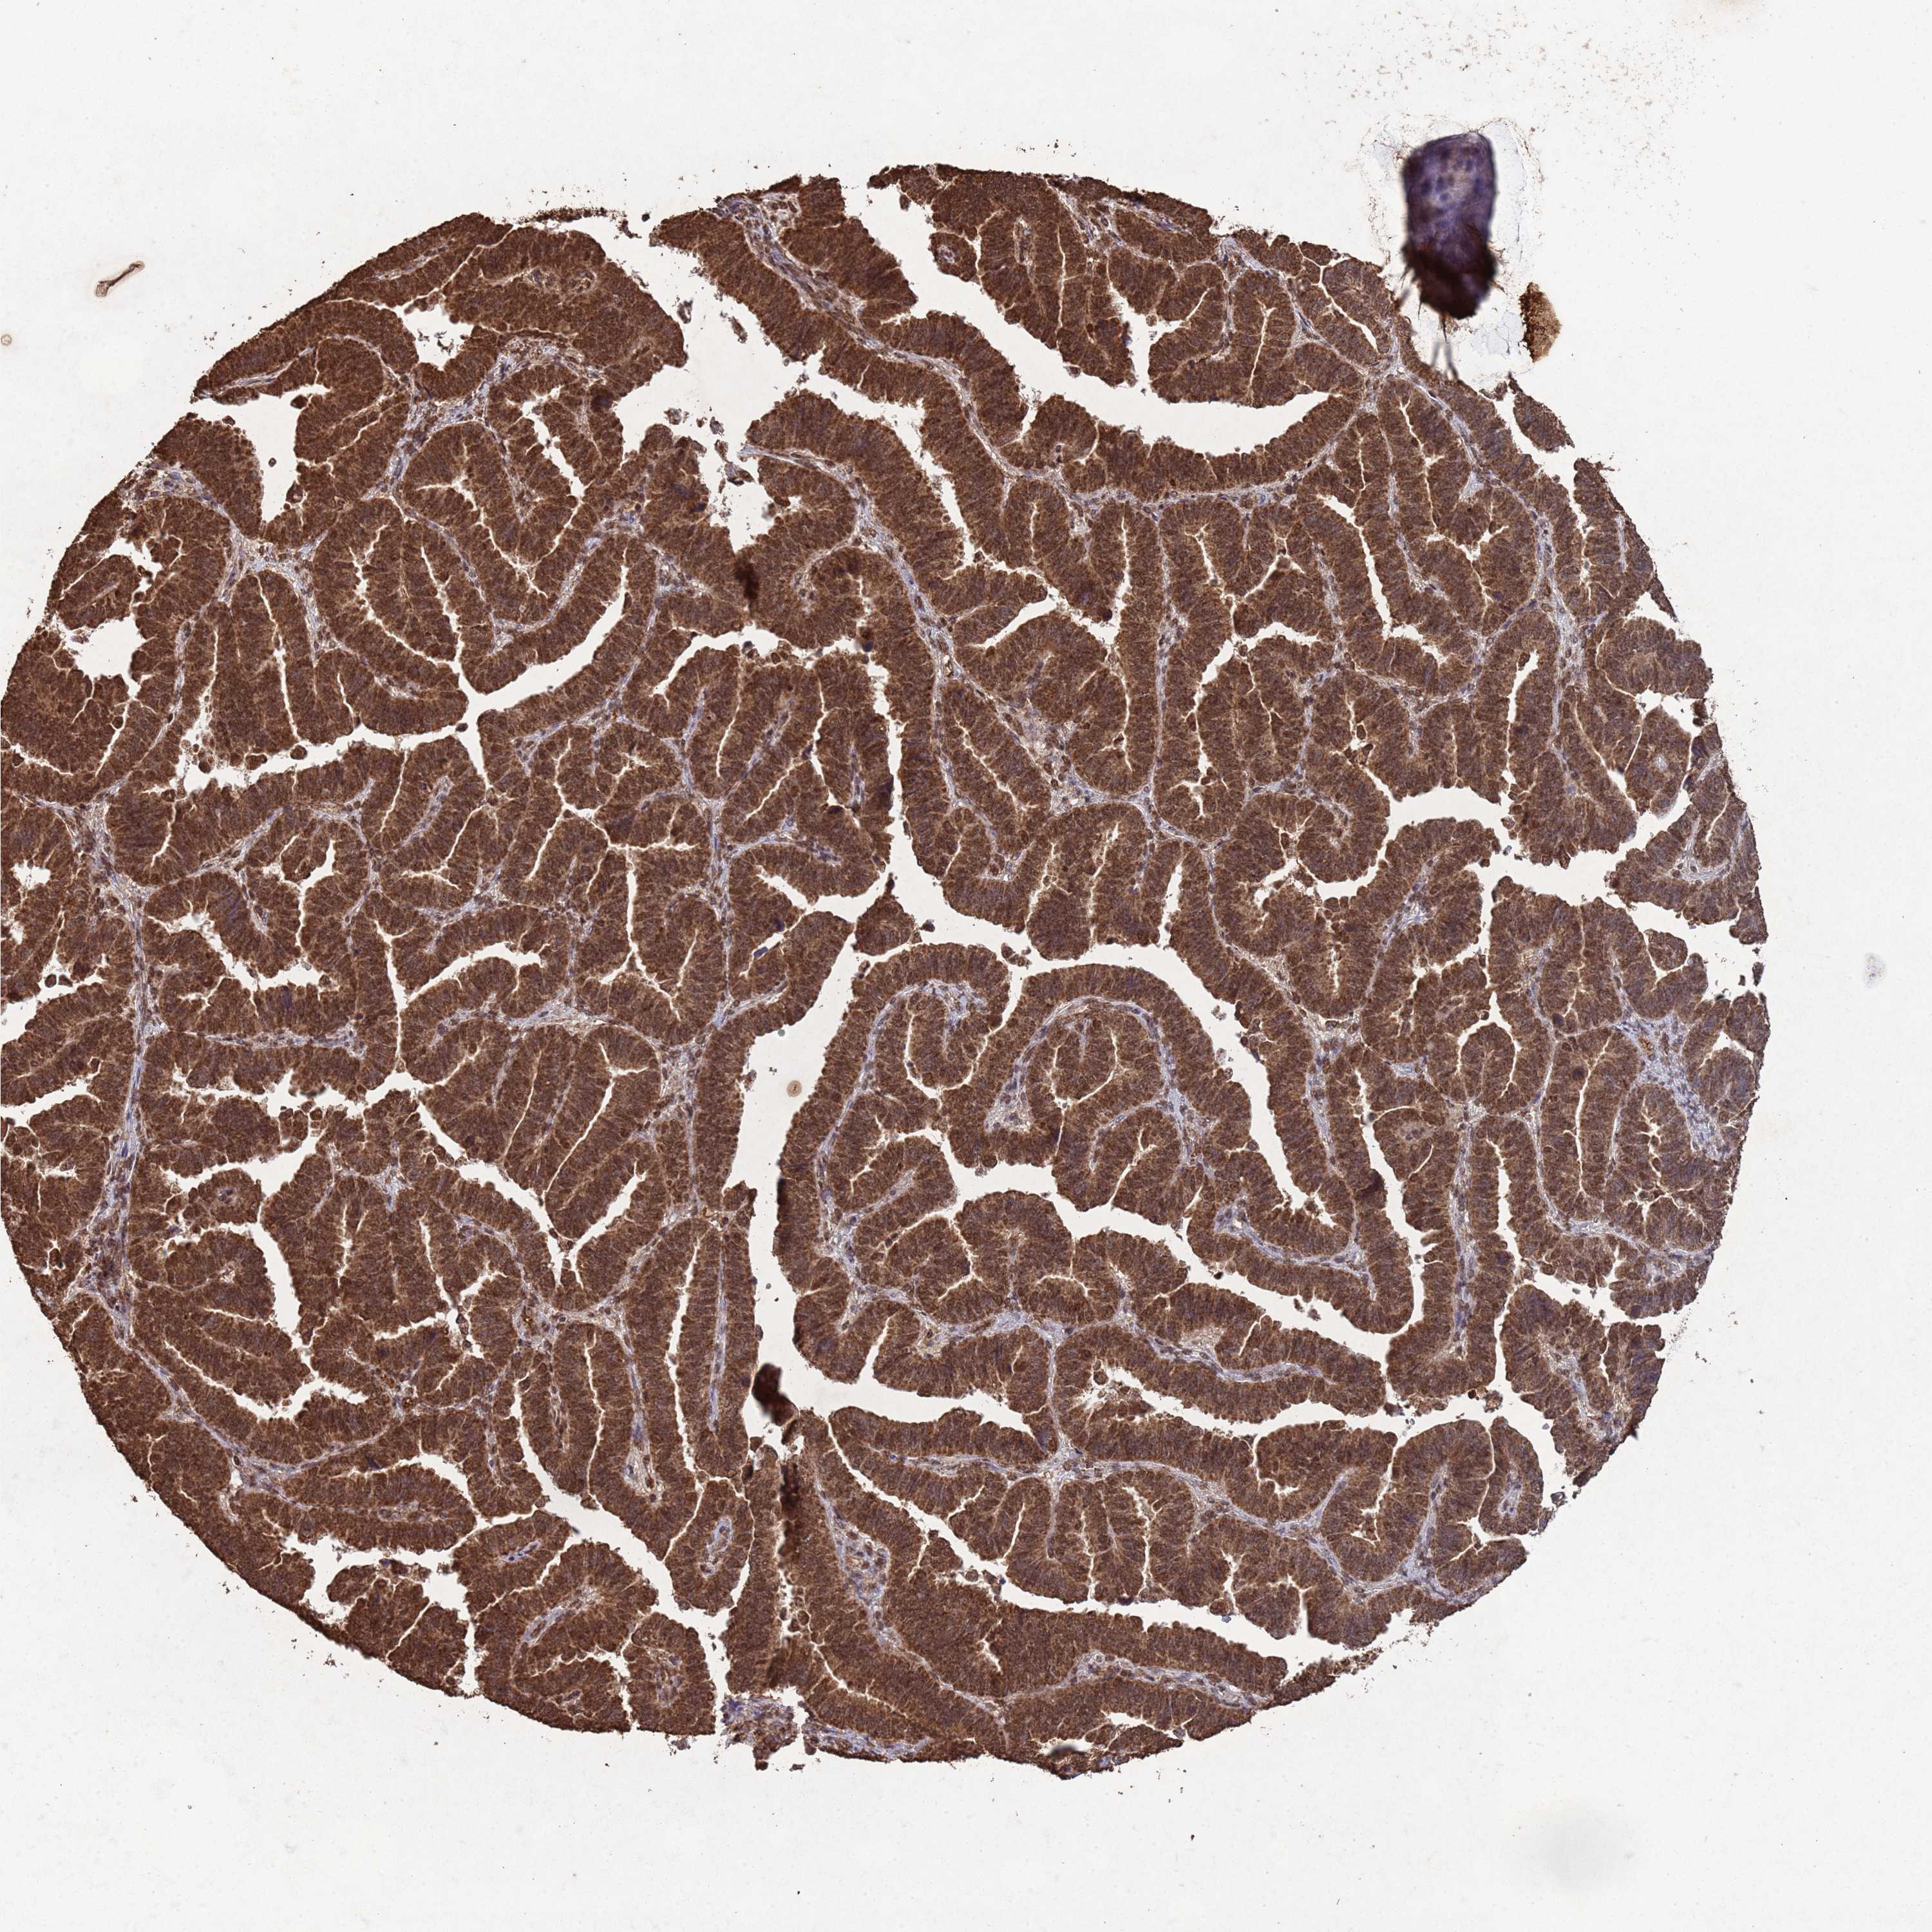

ENDOMETRIAL CANCER - Protein expressioni

A mouse-over function shows sample information and annotation data. Click on an image to view it in a full screen mode. Samples can be filtered based on level of antibody staining by selecting one or several of the following categories: high, medium, low and not detected. The assay and annotation is described here.

Note that samples used for immunohistochemistry by the Human Protein Atlas do not correspond to samples in the TCGA dataset.

Antibody stainingi

Antibody staining in the annotated cell types in the current human tissue is reported as not detected, low, medium, or high, based on conventional immunohistochemistry profiling in selected tissues. This score is based on the combination of the staining intensity and fraction of stained cells.

Each image is clickable and will lead to virtual microscopy that enables deeper exploration of all samples and also displays staining intensity scores, fraction scores and subcellular localization as well as patient and tissue information for each sample.

Antibody CAB045977

Staining

High

Medium

Low

Not detected

Intensity

Strong

Moderate

Weak

Negative

Quantity

>75%

75%-25%

<25%

None

Location

Nuclear

Cytoplasmic/membranous

Cytoplasmic/membranous,nuclear

Adenocarcinoma, NOS